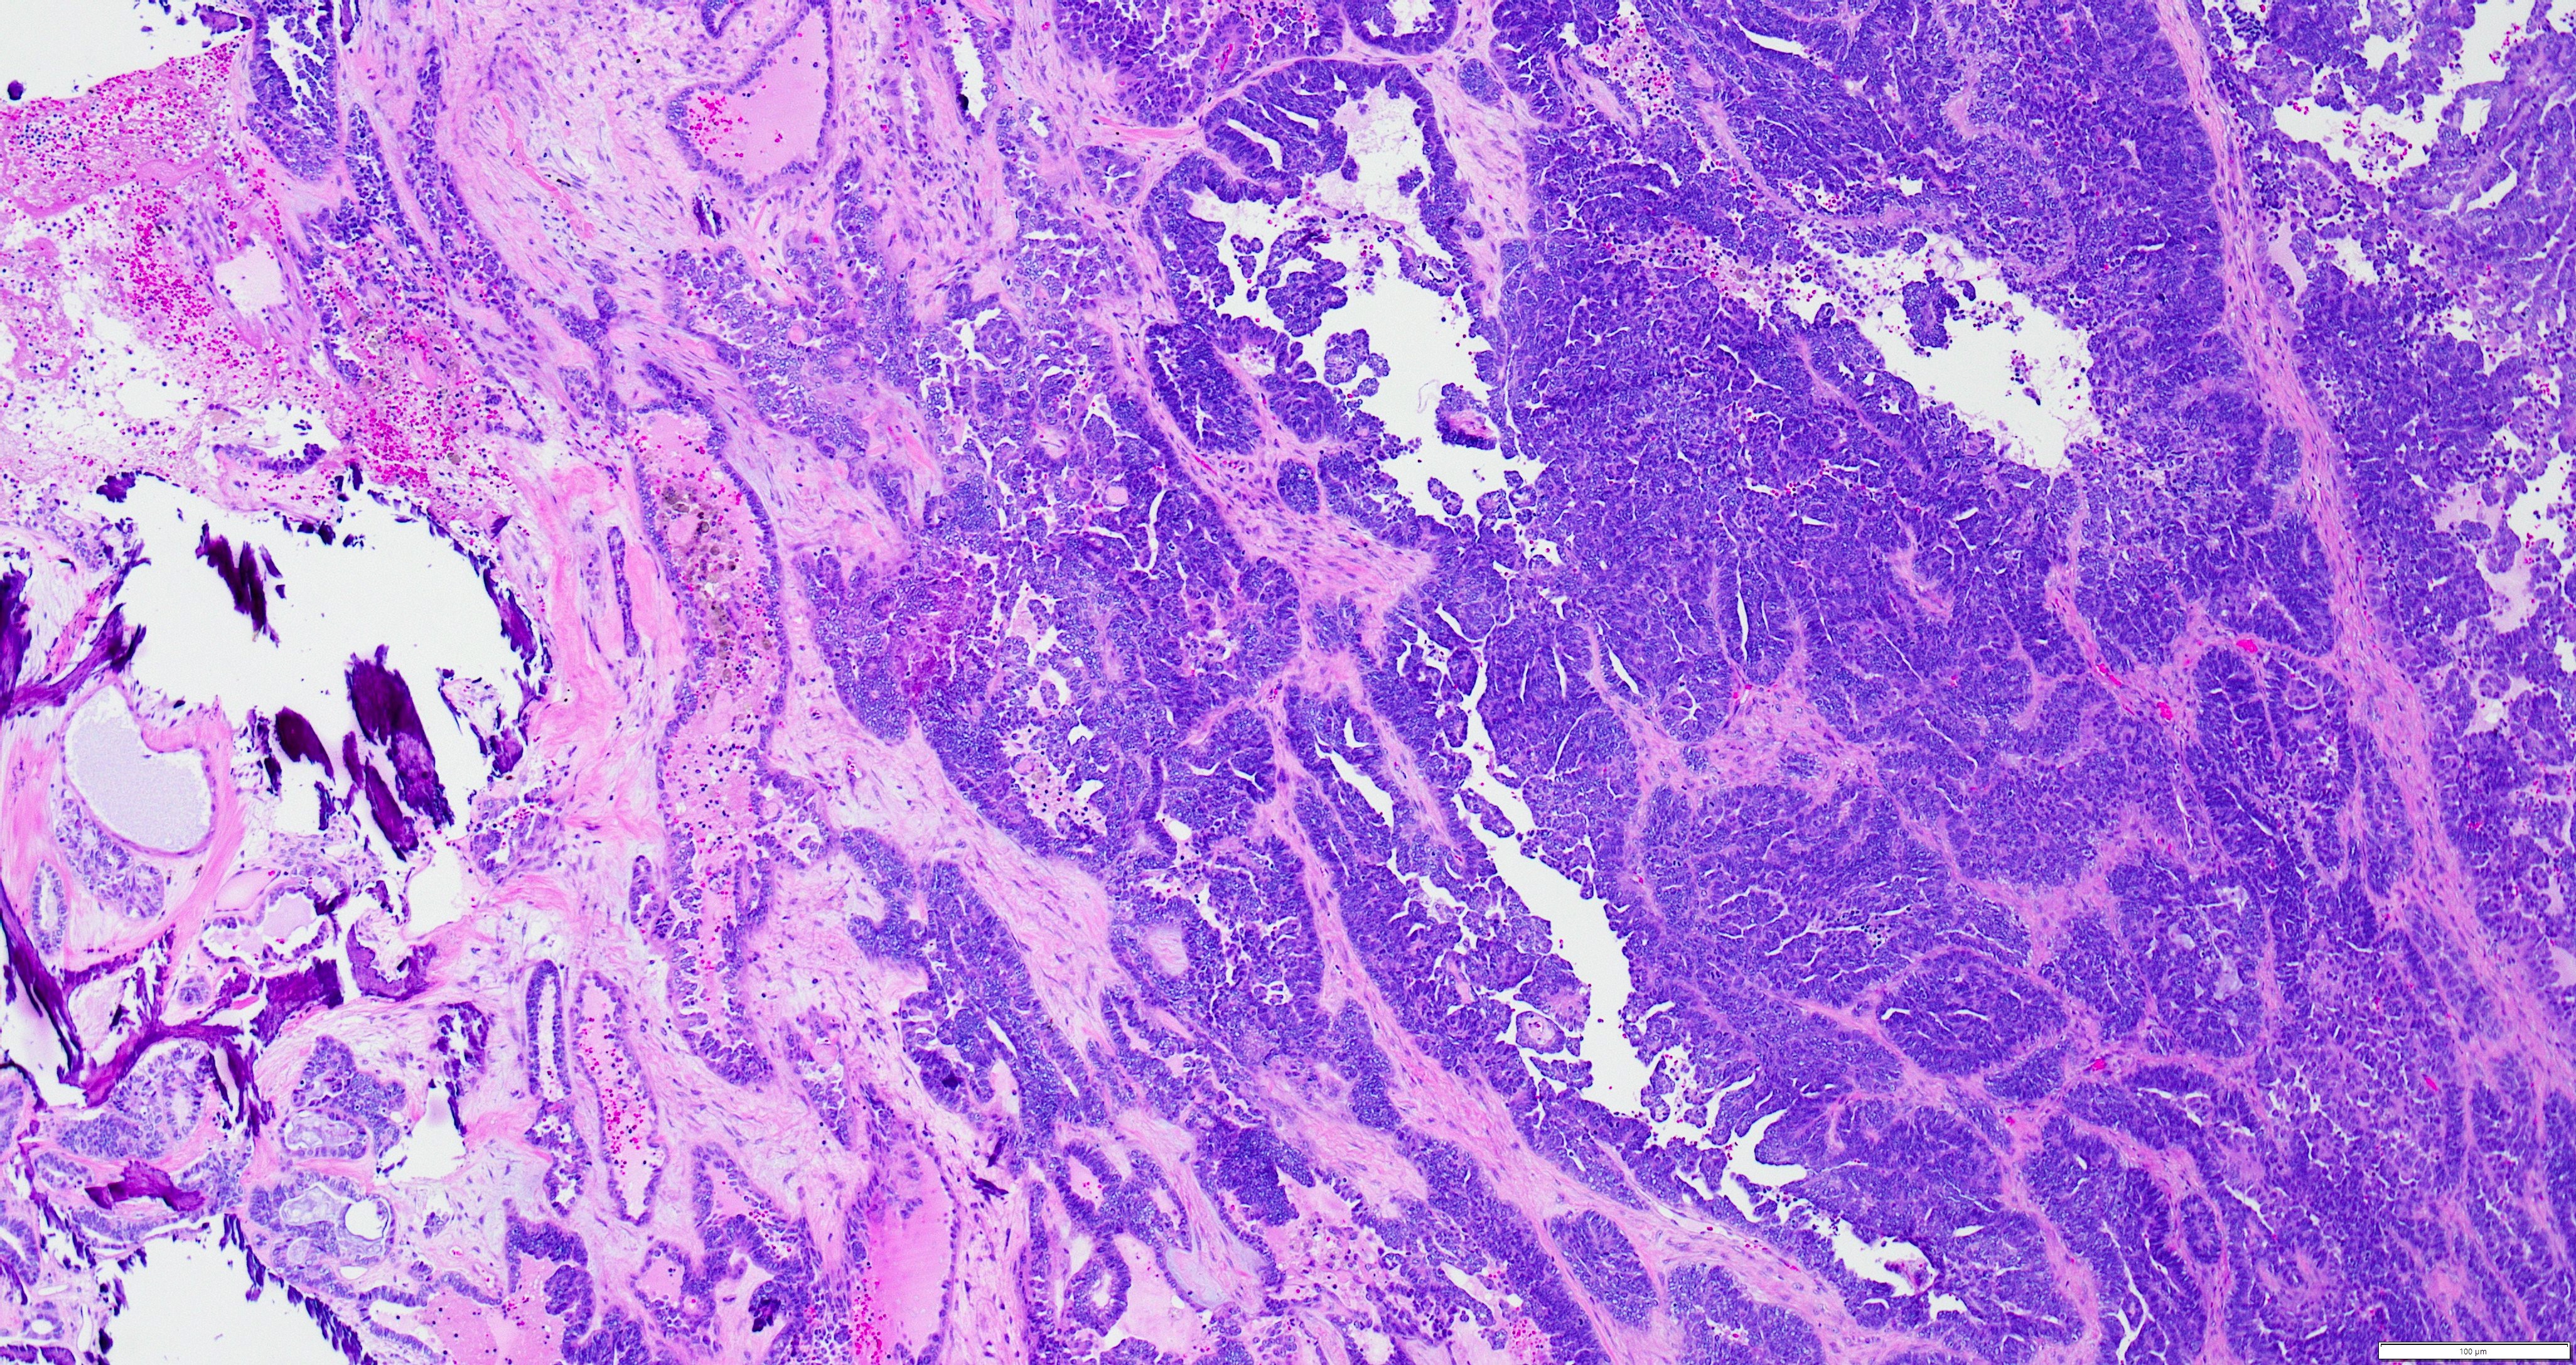

- Variety of histologic patterns that may be present within the same tumor

- Most frequently small tubules with ductal / glandular growth

- Papillary, solid growth, trabecular, retiform, sex cord-like, sieve-like, glomeruloid and spindle cell areas have all been described

- Luminal eosinophilic secretions are characteristic but not always identified

- Tumor cells can be flattened, cuboidal or columnar with mild to moderate cytological atypia

- Clear cell features can be seen but are less common

- High grade cytological atypia is usually not a predominant feature

- Nuclei show vesicular chromatin and nuclear grooves

- Sarcomatoid transformation has been seen in rare instances

- Squamous, ciliated or mucinous differentiation (metaplasia) are not present and there are no associated mesonephric remnants (J Clin Med 2021;10:698)

Microscopic (histologic) images

Contributed by Daniel Graham, M.D., Adele Wong, M.B., B.Ch., B.A.O. and Lucy Ma, M.D.